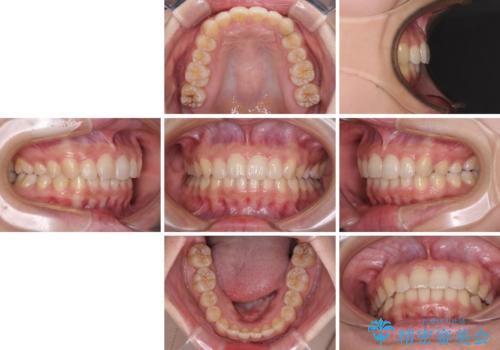

奥歯の倒れた歯を改善 インビザラインでの矯正治療

- 前歯のデコボコと奥歯の不正咬合を気にして来院された患者様です。

左右の大臼歯が全て鋏状咬合(シザーズバイト)になっており、治療が難航することが予想されましたが、インビザラインにより治療を行うこととしました。

最難関と思われたシザーズバイトは比較的短期間で解消されました。

しかし、治療中に2度の出産を経験され、治療期間は長くなってしまいましたが、咬みやすく、清掃しやすい歯列を獲得することができました。